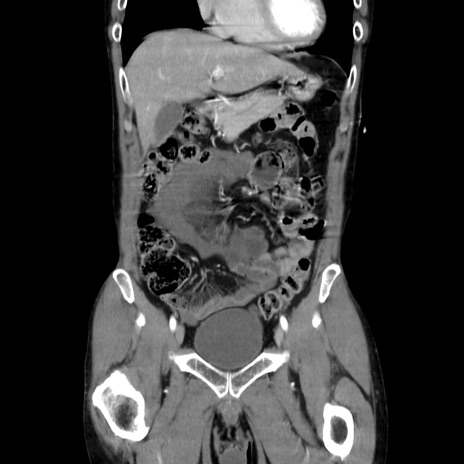

症例37(冠状断像)

【症例】40歳代 男性

【主訴】腹痛

【現病歴】4時間ほど前に電車に乗車中に臍部上より腹痛出現。徐々に増悪し起立困難となり、救急外来受診。生ものは数日食べていない。今朝お雑煮を食べた。

【身体所見】BT 36.8℃、BP 117/84mmHg、HR 91/min、SpO2 97%、苦悶様、腹部:臍上部広範囲圧痛あり、反跳痛±

【データ】WBC 8100、CRP 0.03